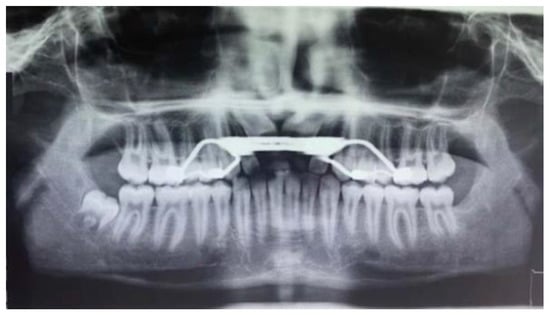

- Ortopanthomography X-ray (OPG X-ray) to evaluate the problem in relation to the entire arch, adjacent tooth and the staging of the eruption of the other dental elements.

| OPG | Orthopantomography X-ray |